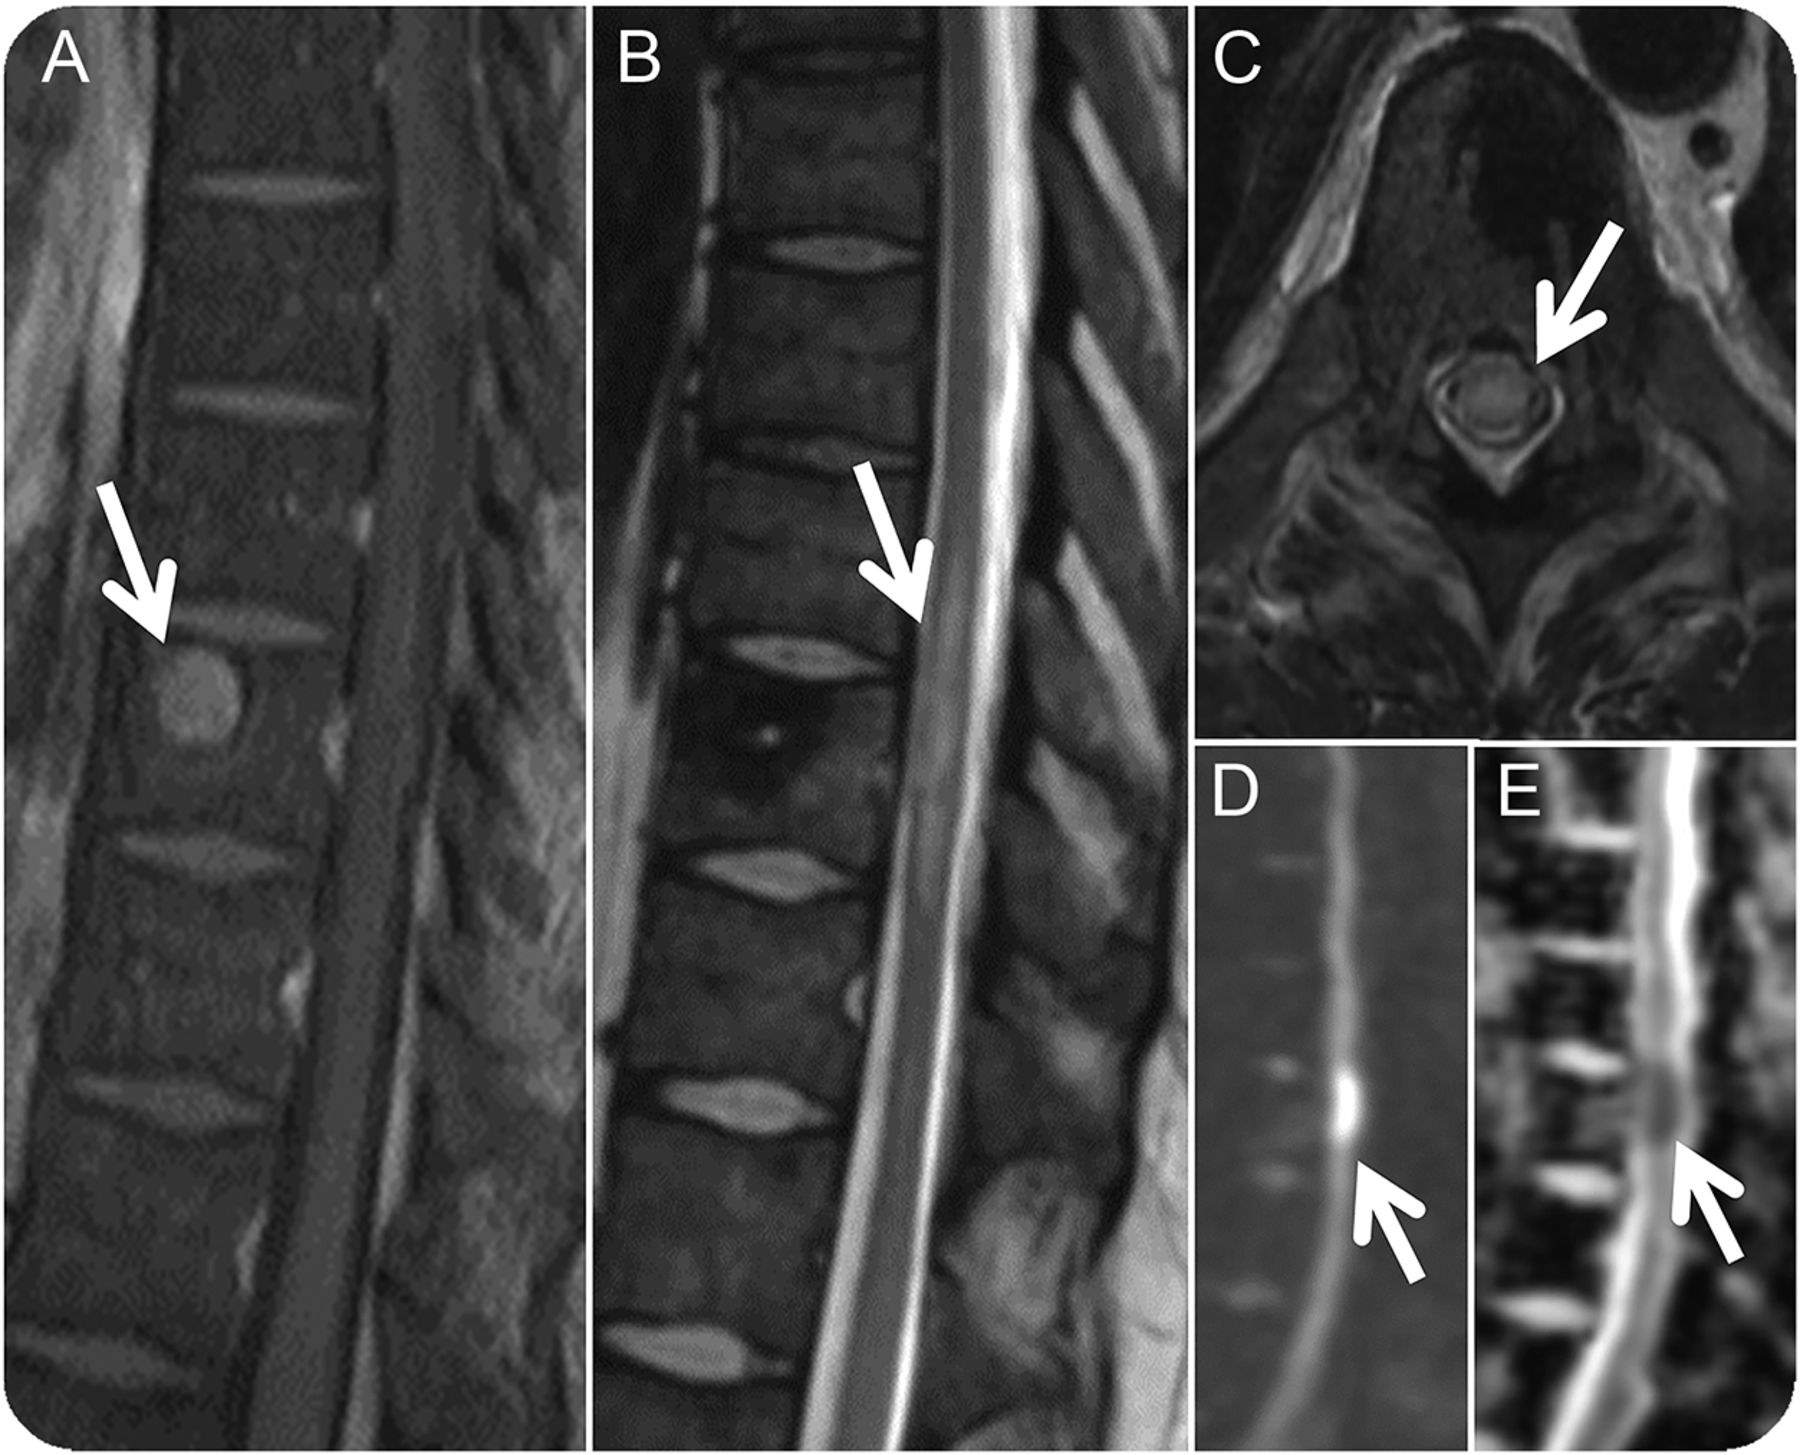

图1

预处理和直接postcryoablation

(A)预处理矢状postgadolinium t1加权图像展示一个增强T10椎体病变(箭头所指)。在t2加权像(中)立即治疗后矢状和轴向,diffusion-weighted形象,表观扩散系数地图展示水肿的绳(箭头,B和C),限制扩散(箭头,D和E)指示细胞毒性水肿。